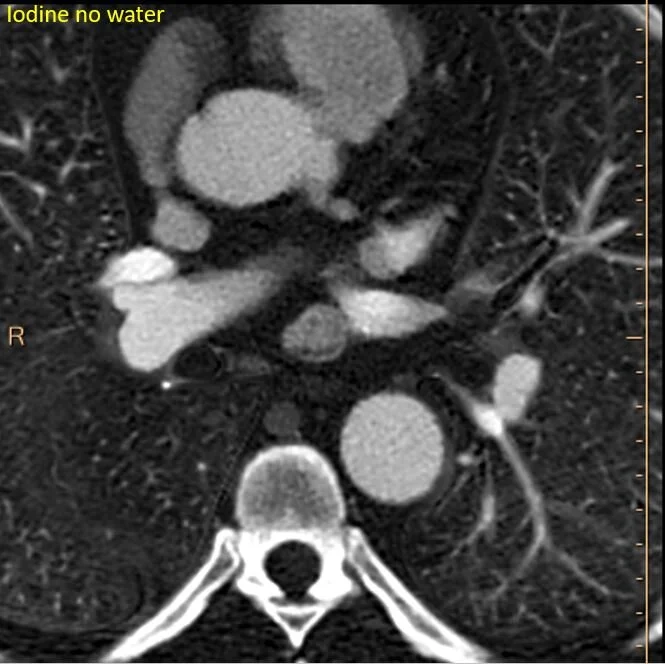

The subcarinal nodule has intense uptake on iodine map.

Quantitatively intense iodine uptake.